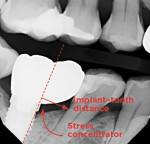

Type 1: Beware of the Cantilever

Although the character Snoopy of comic strip Peanuts fame can be quite charming, when dental radiographs appear in the shape of his profile, caution must be exercised (Figure 2). Type 1 prostheses tend to have a greater risk for developing complications such as abutment screw loosening, broken crowns, cementation failure, and a fractured abutment or implant.1-3 Moreover, healthy teeth in close proximity may be prone to developing caries, often due to food traps created by this type of prosthesis.4 Many of the complications associated with a type 1 prosthesis shape are related to a principle in mechanical engineering called a "cantilever," which allows linear forces acting at a distance to be converted to rotational or bending forces.

Furthermore, rotational forces challenge practically all aspects related to dental implants. Implants are designed to support loads being applied in an axial direction; thus, when subjected to rotational or bending forces, they can break or fatigue easily.5 Similarly, small abutment screws bend due to torsional loads, which can cause screw loosening or fracturing as well. To effectively separate an internal conical connection between abutment and implant, one must distort the interface by applying off-axis or rotational forces.6 This will generate an asymmetric load that will do just that. Ceramics and bonding cements tend to be their strongest when exposed to compressive forces; however, the opposite is true when subjected to tension.7 When rotational forces are applied, these materials become placed in an environment of tensile stress where they can easily break apart and fail. As a result, it is critical that both ceramic and cement components remain within their most suitable operating conditions for optimal performance.

Thus, if presented with a cantilever, the clinician should watch for potential complications. When a type 1, or Snoopy-like, implant restoration radiograph is noted, the clinician should set the patient's expectations straight and determine an ideal treatment option. For instance, there is a strong likelihood of impending screw loosening with a type 1. Clinically, the risks can be mitigated by ensuring the cantilever end of the prosthesis cannot hold shimstock. Also, by addressing this concern with patients up front and centering them in their care plan accordingly, they are more likely to be better prepared for potential complications down the road.